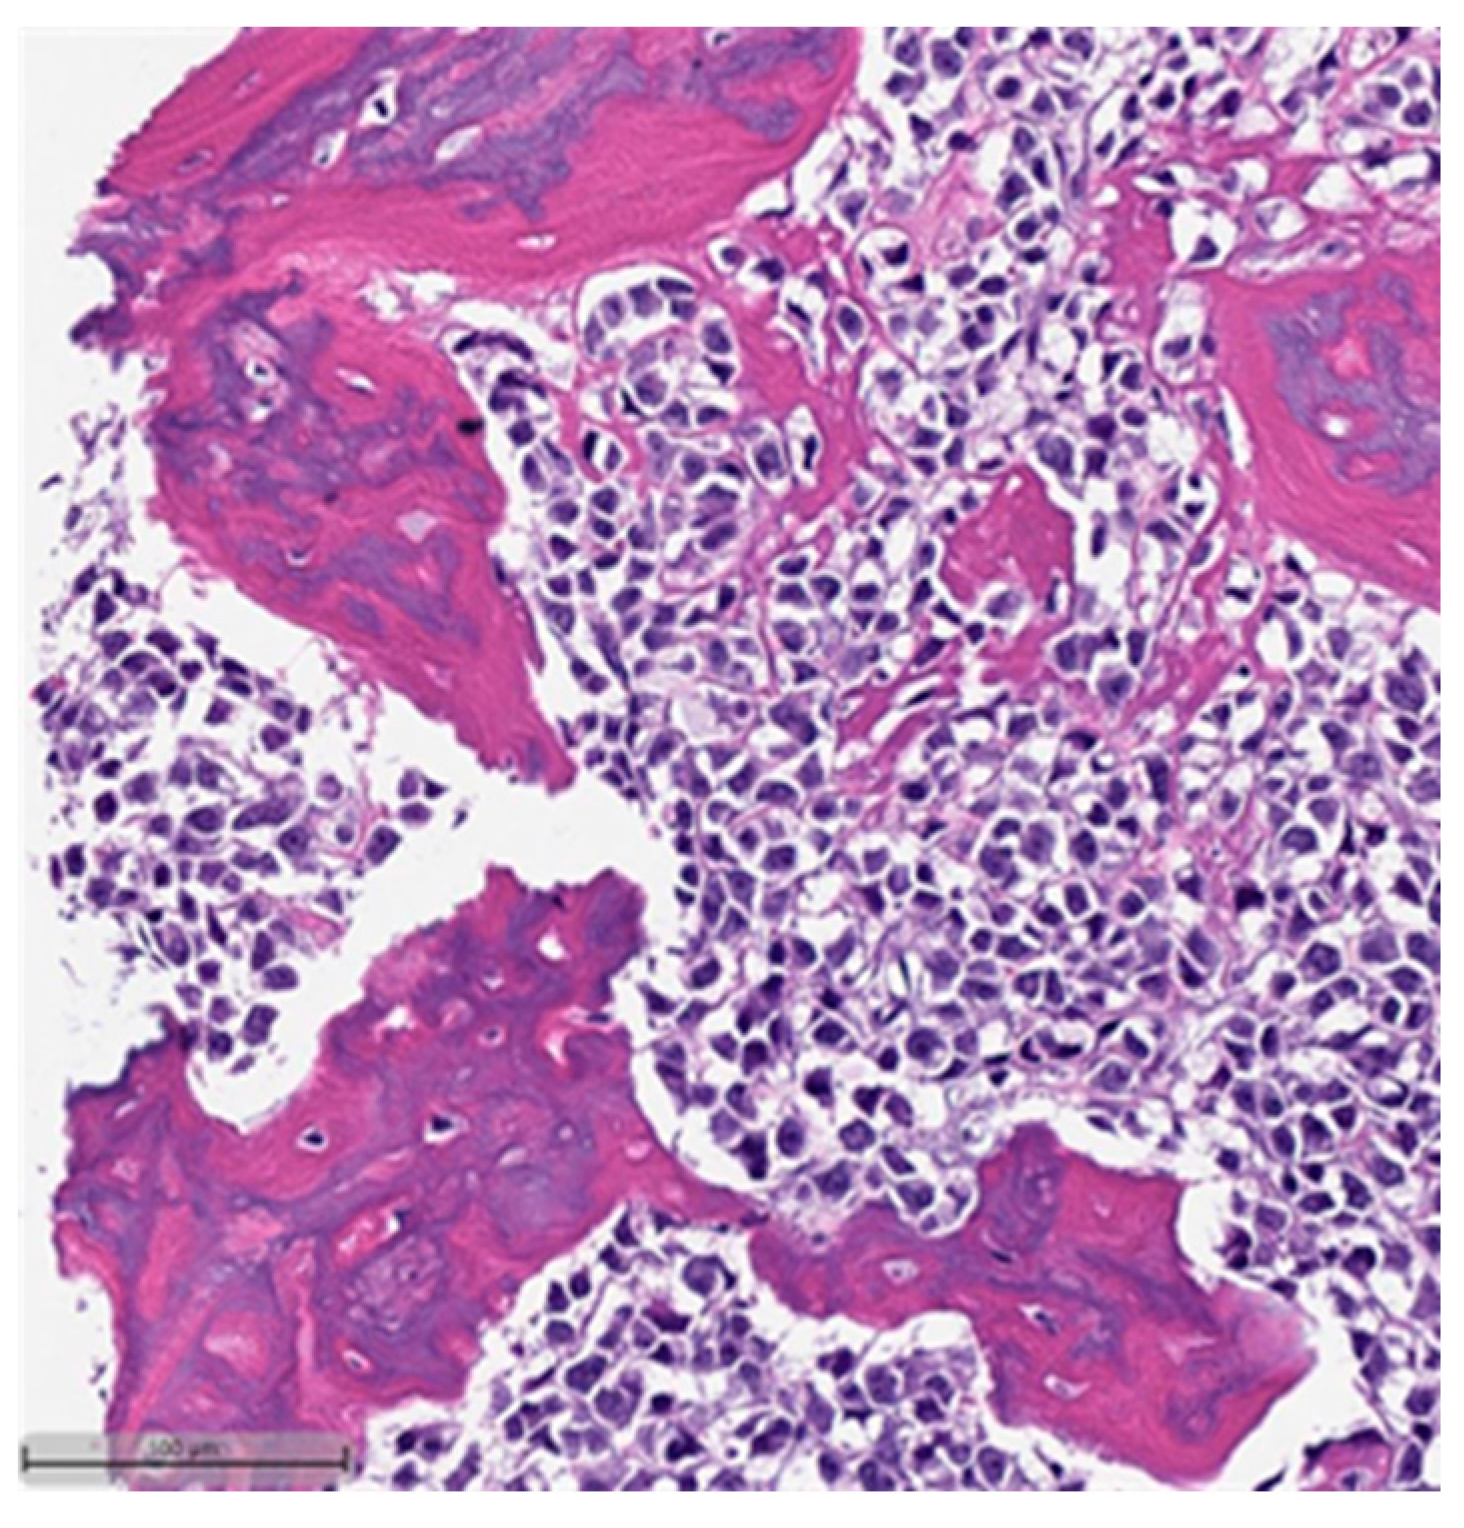

Figure 1. Squamous cell carcinoma component. This case also showed myxoid matrix areas (H&E, 20×).

Figure 2. Squamous cell carcinoma component (H&E, 20×).- Spindle cell carcinoma (SpCC) (Figure 3);